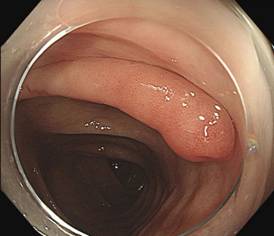

陈先生28岁,主诉间断腹胀1月余,肠镜检查于横结肠发现息肉样病变,表面正常黏膜覆盖、充血,靠近根部可见扩张血管。

在与陈先生阐明病情后,医生采用套扎术切除